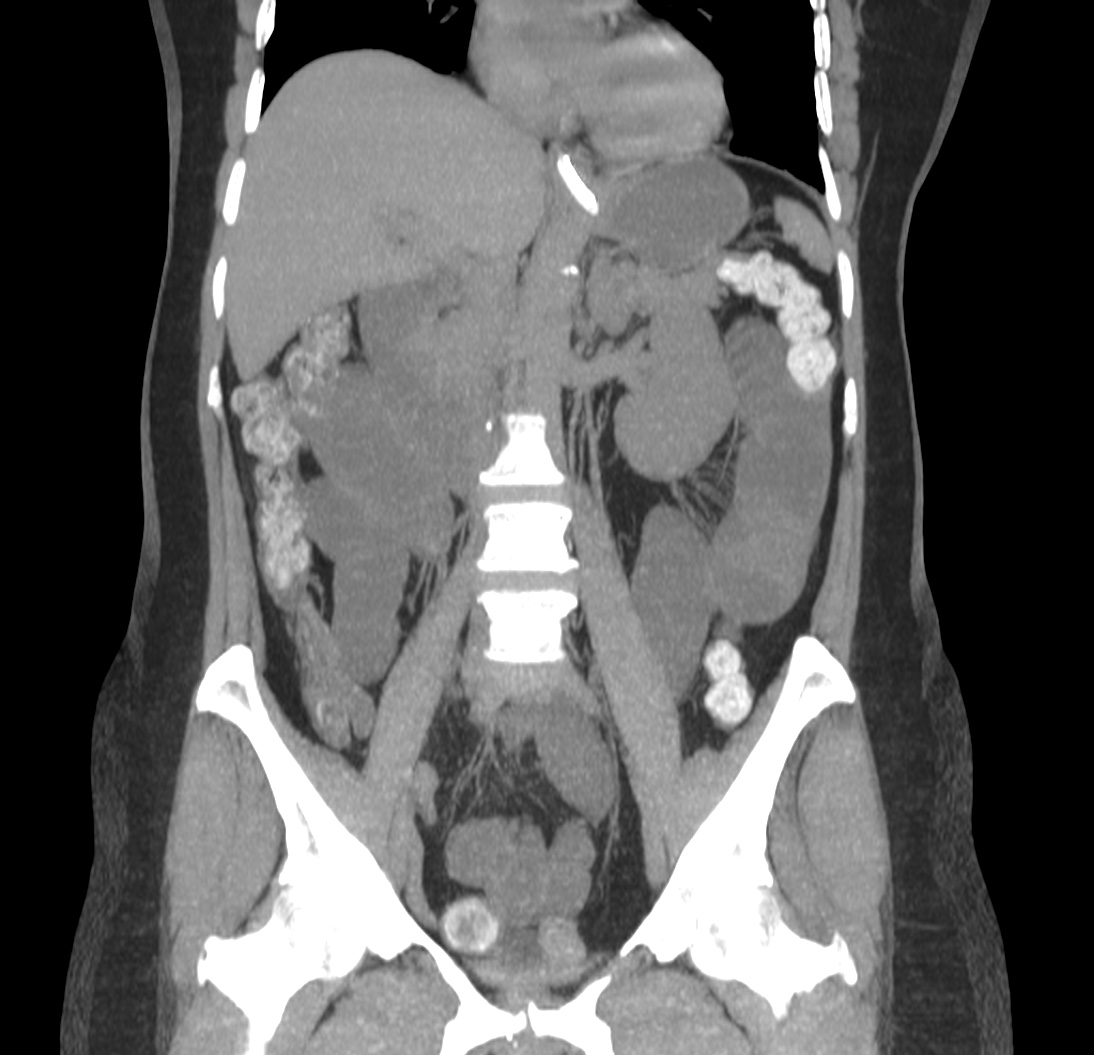

Se realiza un TC abdominal sin contraste:

Observar como posterior a la litiasis hay un cambio de calibre, el segmento que queda de ileon y el colon no están distendidos.

No encontramos ante un Ileo biliar, una obstucción intestinal mecánica ocasionada por una litaisis enclavada en el íleon terminal. La paciente estaba colecistectomizada, por tanto, lo más probable es que haya sido producido por una litiasis residual que pasó desapercibida.